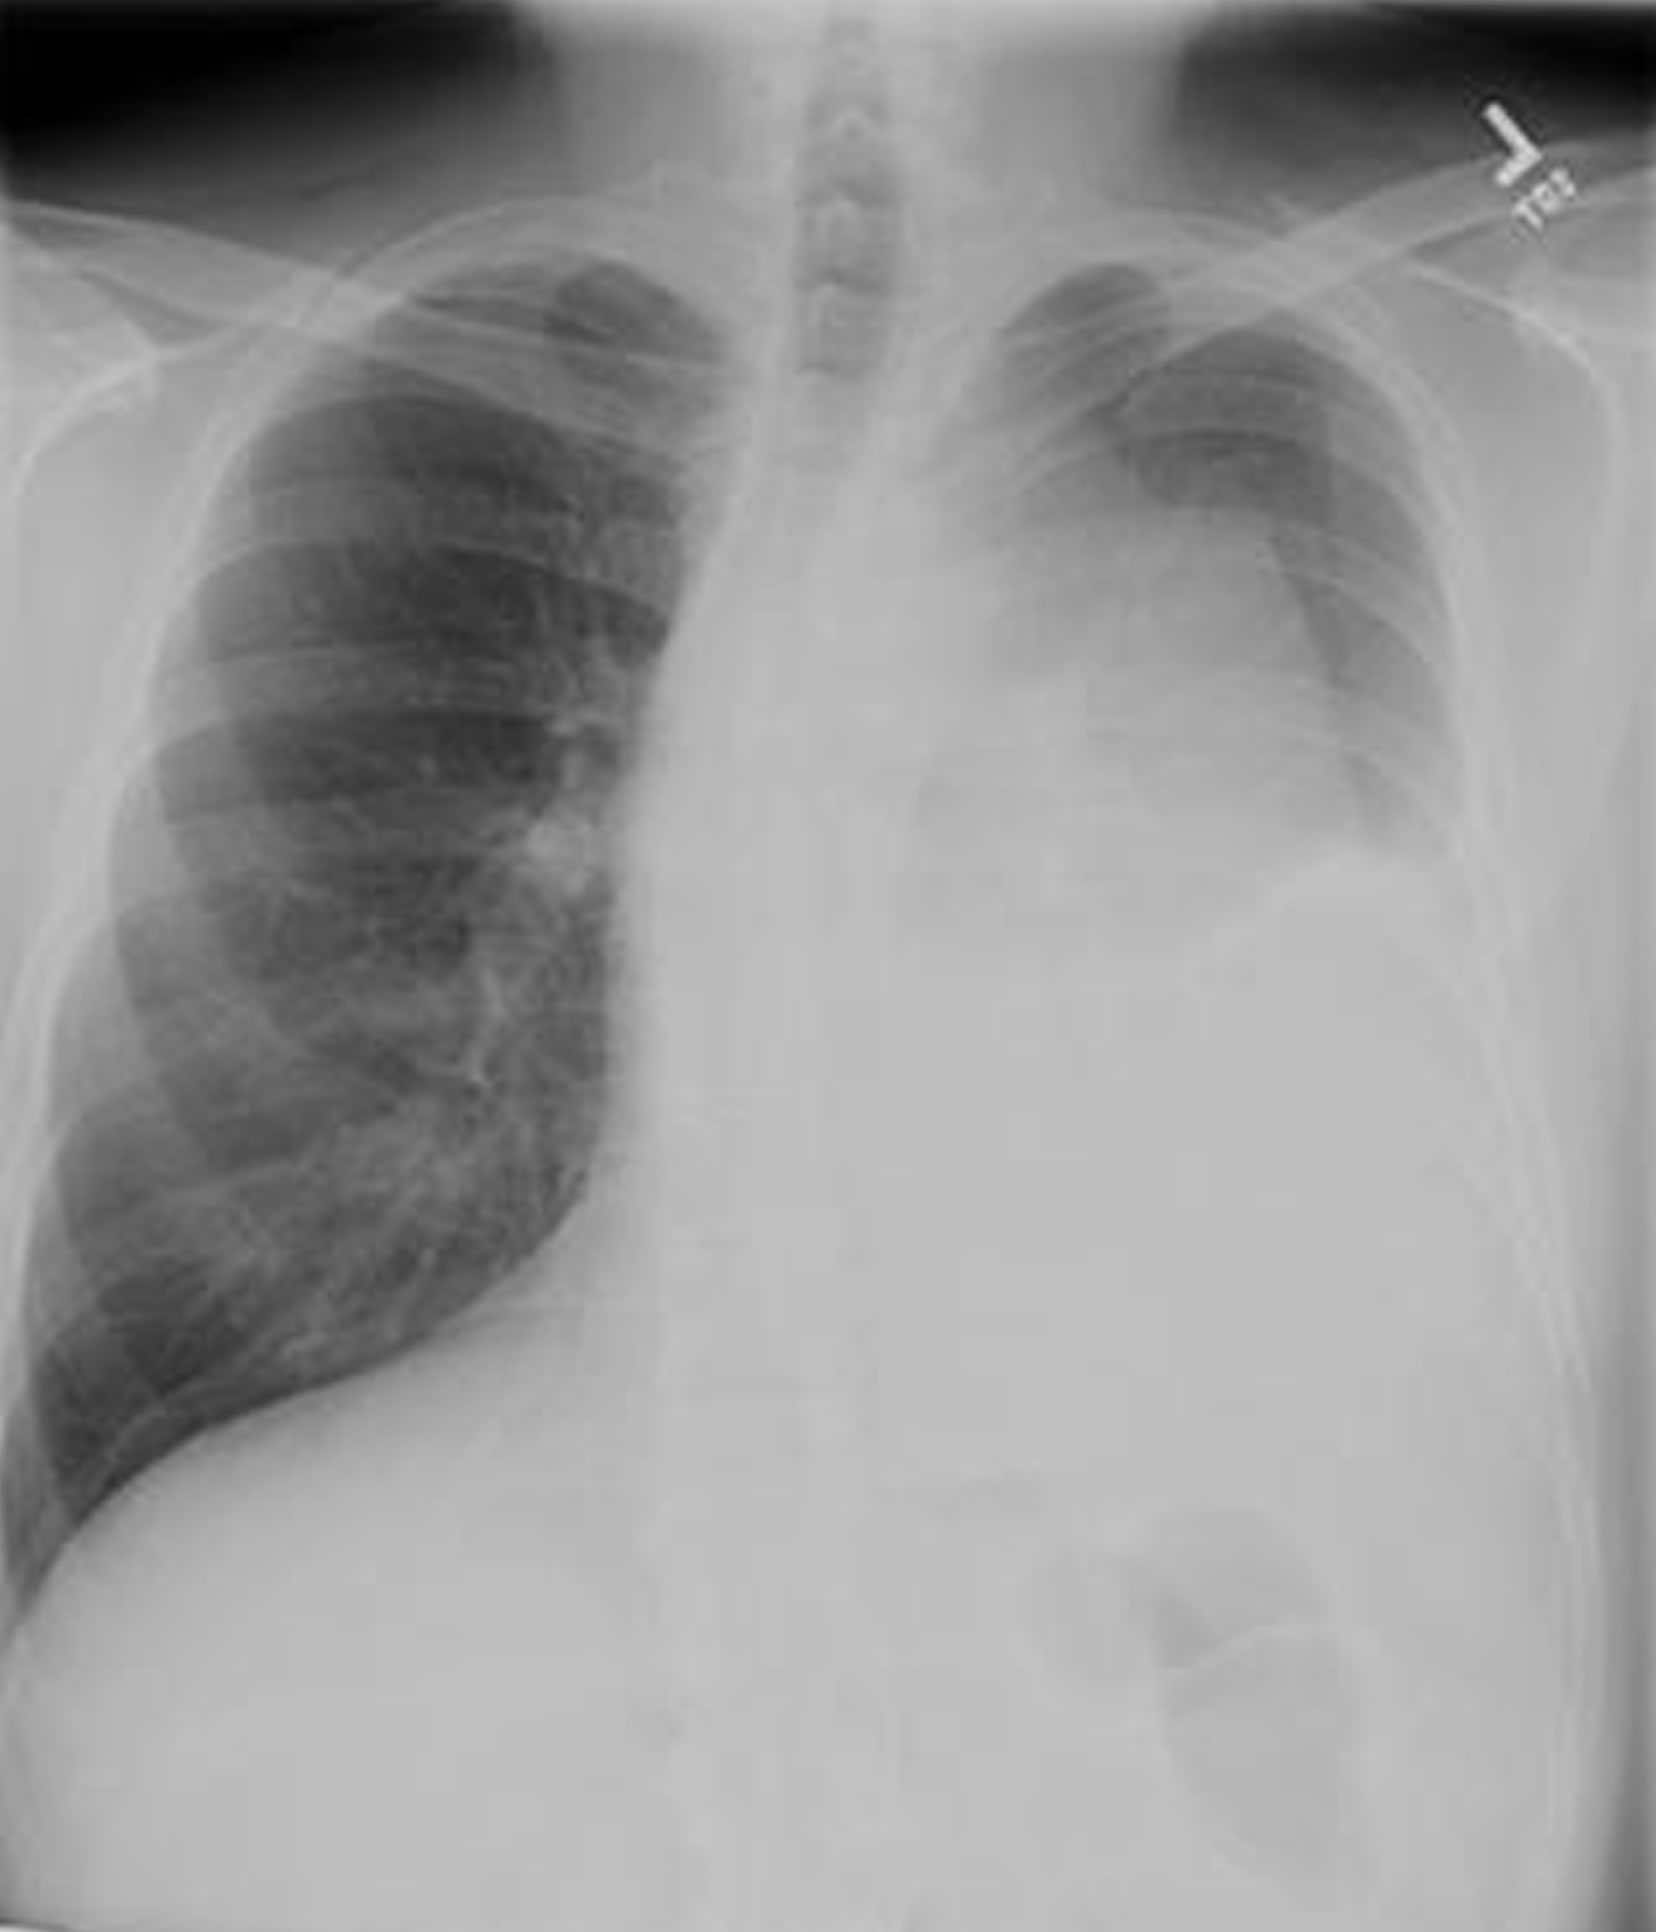

Any anterior mediastinal mass (Figures 1, 2) must be considered suspect for germ cell tumor, especially in a young male. Errors in diagnosis are not uncommon and can result in mismanagement of a potentially curable patient. All patients with an anterior mediastinal mass should have alpha-fetoprotein (AFP), β-human chorionic gonadotropin (β-HCG), and lactate dehydrogenase (LDH) levels drawn at the outset. The different types of germ cell histologies are shown in Figure 3.

Figure 1a: Chest radiograph of mediastinal germ cell tumor

Figure 1b: Chest radiograph of mediastinal germ cell tumor